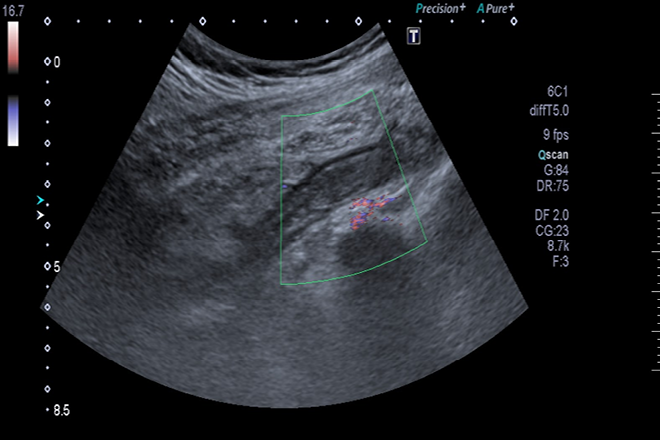

El diagnóstico de CHC se fundamenta en pruebas de imagen o biopsia. En el caso de estudios radiológicos, no se requiere biopsia si los hallazgos característicos están presentes en nódulos de 2 cm o más. Para ello, basta un estudio contrastado trifásico mediante tomografía computada (TC) o resonancia magnética (RM).

Importancia del ultrasonido (US) en el diagnóstico

El objetivo principal de este estudio fue analizar la frecuencia de complicaciones como el CHC y la TP en pacientes cirróticos, destacando el papel fundamental del US como primera técnica de imagen para su detección.

Los resultados de un estudio realizado en 211 pacientes con cirrosis a lo largo de 4 años revelaron la alta eficacia del US en la detección de CHC en casos de daño hepático crónico sintomático.

Estos hallazgos resaltan la importancia de realizar un screening con US para identificar tempranamente el CHC en pacientes con cirrosis, evitando así llegar a etapas avanzadas donde las opciones terapéuticas son limitadas.

Este estudio subraya la relevancia de utilizar un método tan accesible y seguro como el US para la detección precoz de complicaciones en pacientes con cirrosis hepática. Realizar un screening con US cada 6 meses en estos pacientes puede identificar oportunamente el CHC y mejorar las opciones de tratamiento convencional.